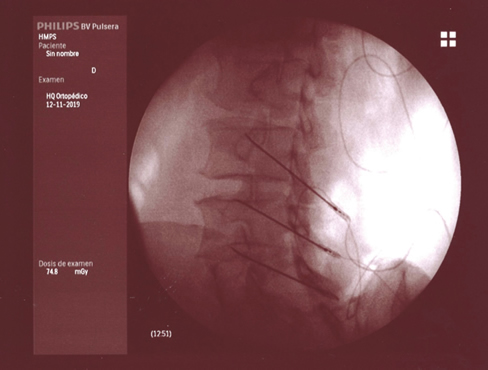

Figura 2